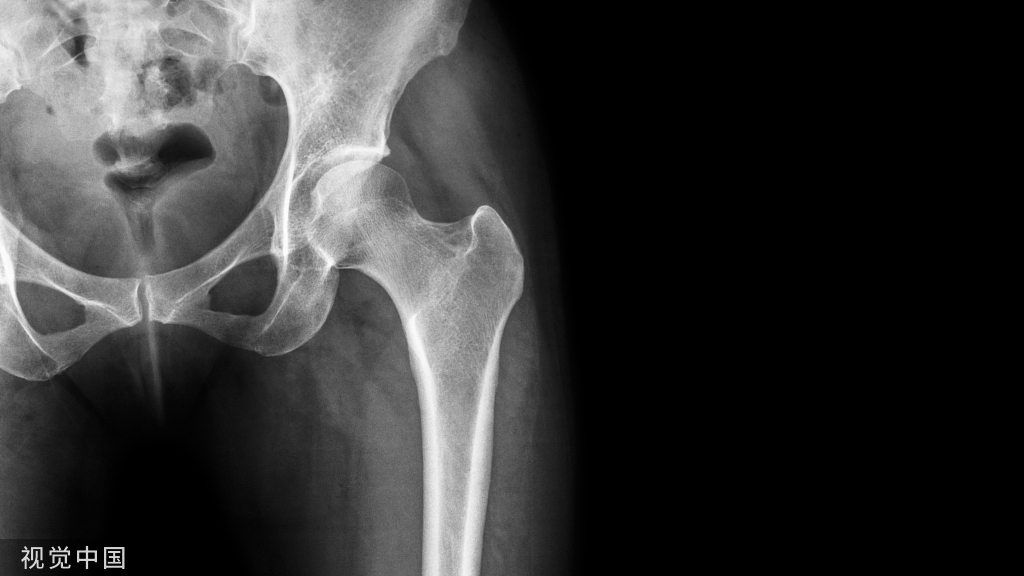

老年 KOA 是一种以膝关节软骨退变、继发性骨赘形成、软骨下骨硬化、滑膜炎症等为主要特征的慢性退行性疾病,是 OA 中发病率最高的一种[8]。大于60岁的老年人多见(世界卫生组织对老年人的定义为60周岁以上的人群),占了总患病率的65.2%。